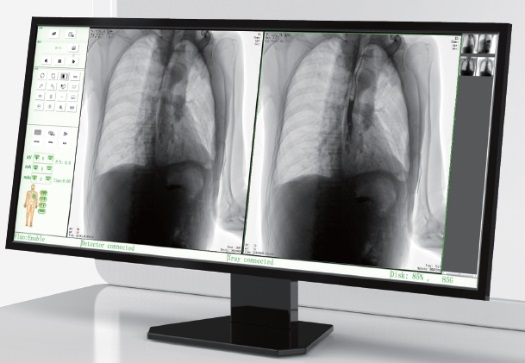

高品質影像鏈 讓您看的更清晰 PLX8500C/D

● 無縫對接醫(yī)院PACS系統(tǒng),幫助實現信息共享、遠程診斷。